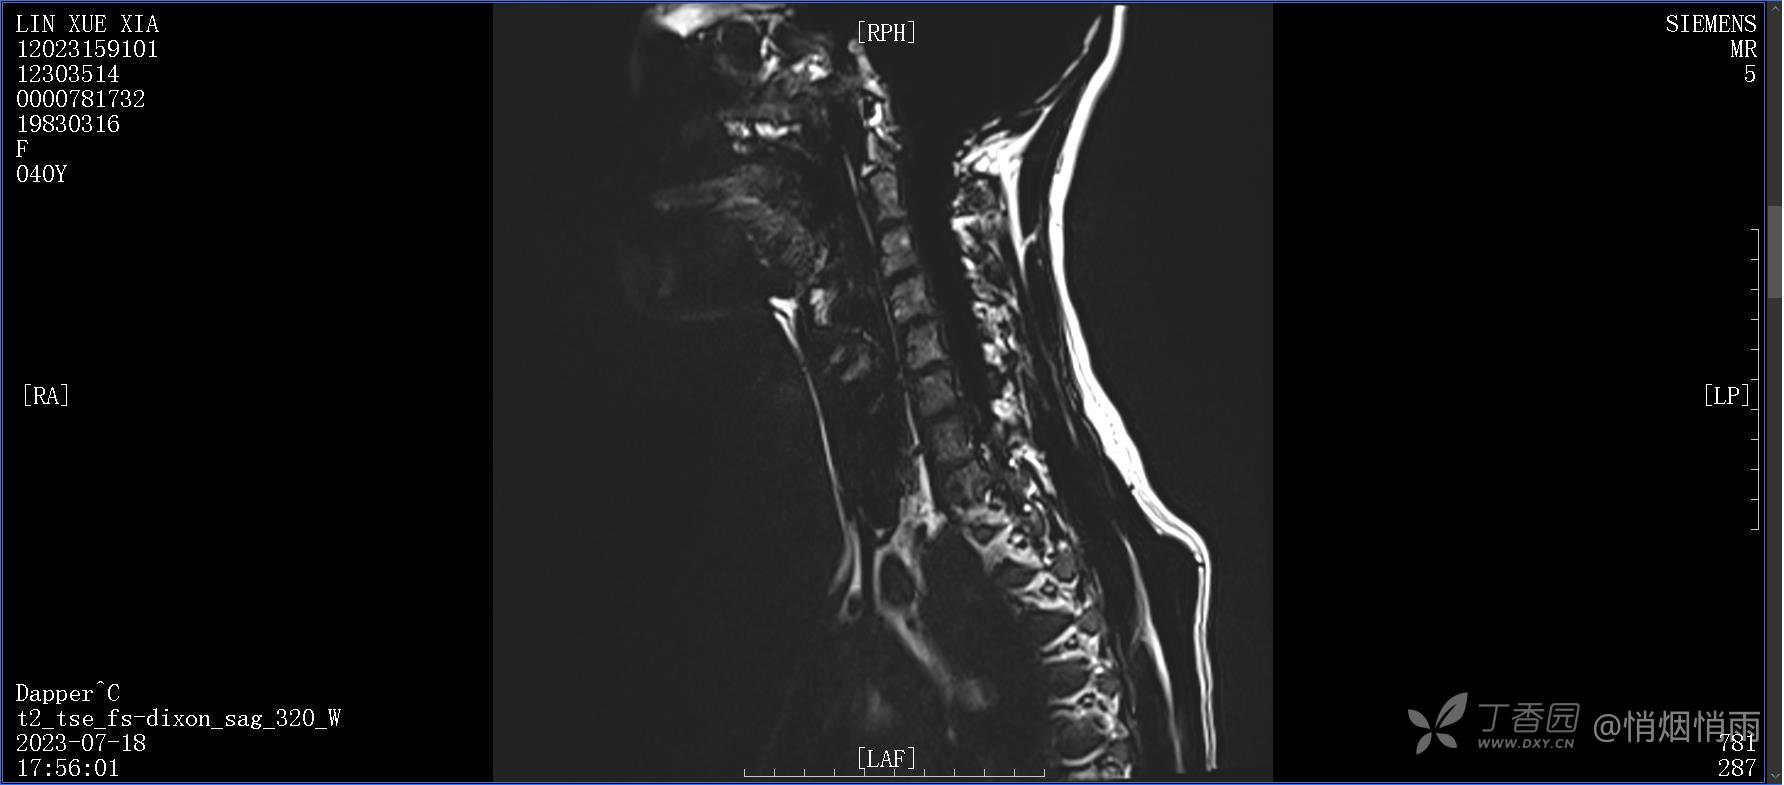

NeurothinkerZ 推荐患者女性,40岁,因右肩背部疼痛班活动受限4日余入院(2023-07-17)。

病史:入院前4天无明显诱因突然感右肩背疼痛伴随活动受限,自行口服依托考昔、艾瑞昔布等药物治疗,院外应用肩关节局部手法按摩等,均无明显改善。外院门诊诊为颈椎病。自诉既往多次“胸椎小关节紊乱”于当地诊所行手法按摩,治疗后好转,否认慢性疾病病史、外伤史、手术史,诉青霉素过敏,无其他药物食物过敏史,否认吸烟史、饮酒史,月经正常,经量正常。

目前的诊断,暂时依据辅助检查诊为肩袖损伤,但是患者疼痛的性质和特点,却不是单纯的肩袖损伤所致。考虑过胸廓出口综合征,但是该疾病会出现肩胛区的疼痛吗?(由于考虑到费用的问题,没再进行下一步的检查)带状疱疹会有如此的症状吗?